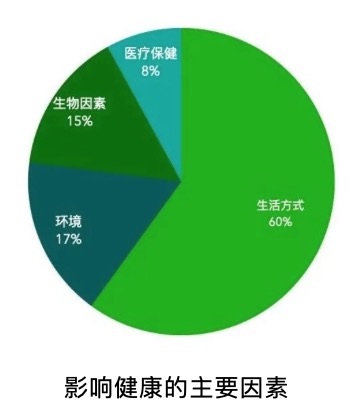

- 运动处方,是解决慢病人群的低成本干预策略! BuGu ,2020-05-27

- 中国现有确诊慢性病患者近3亿,其中一半慢性病发生在65岁以下人群; 得了慢性病后,临床医学及药物干预有限; 体力活动不足和静坐少动是当今非传染性疾病第一独立因素―-WTO2011运动是预防和治疗疾病的低成本干预策略,针对肥胖、糖尿病、心脑血管疾病,可以提高心肺耐力,减少动脉粥样硬化,缓解抑郁。 .....